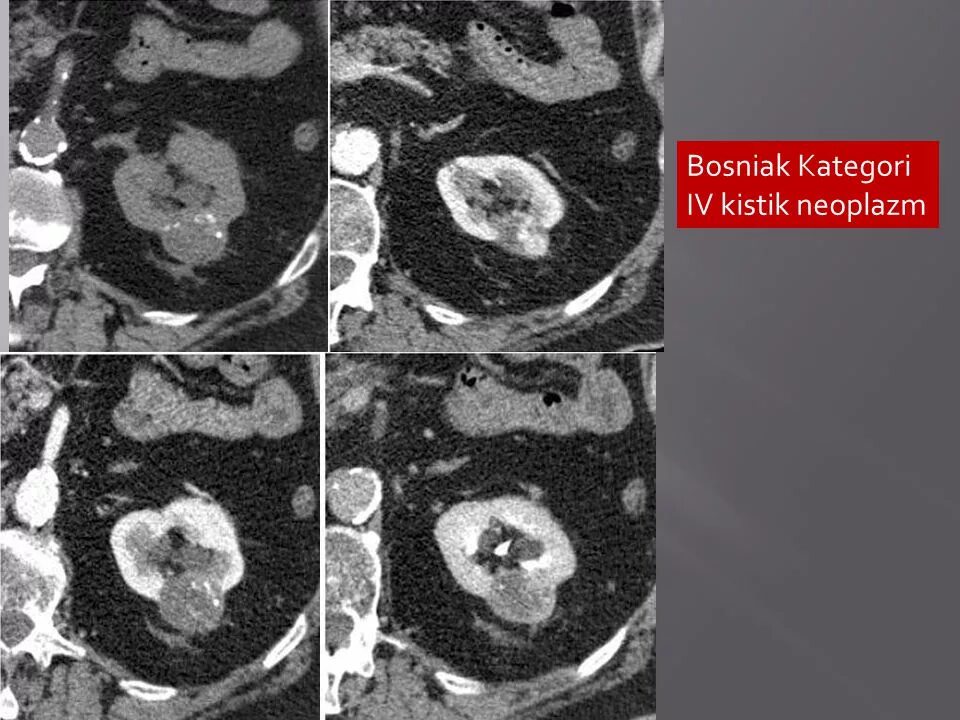

Кисты почек bosniak